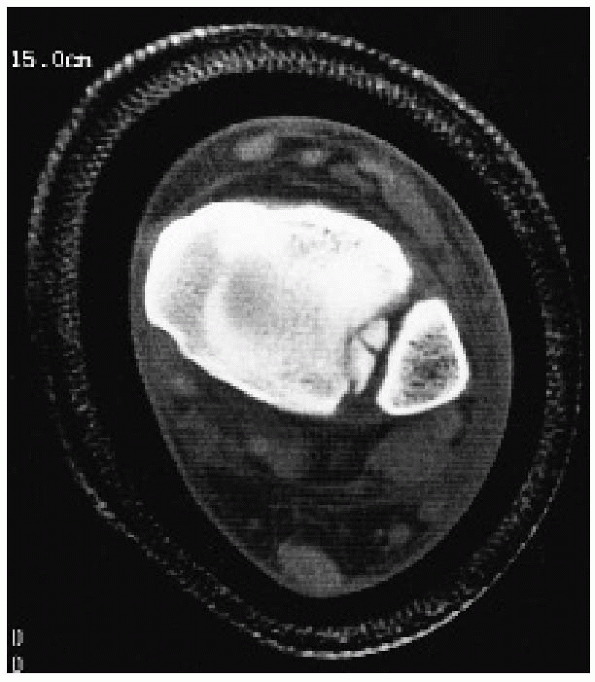

evaluation complex fractures of the distal tibia and ankle in patients

with open physes. Smith and associates174

found that of 4 patients with acute (3 to 10 days) physeal injuries,

MRI showed that 3 had more severe fractures than indicated on plain

films (Fig. 26-23). Early MRI studies (3 to 17

weeks after injury) not only added information about the pattern of

physeal disruption but also supplied early information about the

possibility of growth abnormality. MRI has been reported to be

occasionally helpful in the identification of osteochondral injuries to

the joint surfaces in children with ankle fractures.95

obtained MRI studies on 14 patients with known or suspected growth

plate injury. The MRI detected five radiographically occult fractures

in the 14 patients, changed the Salter-Harris classification in two

cases, and resulted in a change in treatment plan in 5 of the 14

patients studied. These studies would seem to contradict an earlier